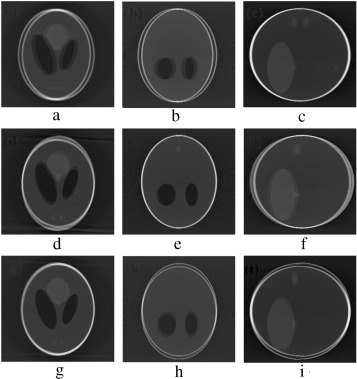

In order to validate the functionality of our proposed Marker-Based Motion Detection (MBMD) and artifacts mitigation technique (MB_FDK algorithm), we need to first simulate motion artifacts using our modified 3D Shepp–Logan phantom. For simulating motion artifacts, we need to perturb the 3D Shepp–Logan phantom during data acquisition time. Using the modified X-ray projection equation  [17] , which incorporated three translational Failed to parse (MathML with SVG or PNG fallback (recommended for modern browsers and accessibility tools): Invalid response ("Math extension cannot connect to Restbase.") from server "https://mathoid.scipedia.com/localhost/v1/":): {\textstyle (t_x,t_y,t_z)}

and three rotational (roll, pitch, yaw ) parameters of motion, we simulated several abrupt and gradual variations of motion on the 3D Shepp–Logan phantom. The cone-beam parameters listed in  Table 2  are used for our simulation. For abrupt variation of motion, we perturbed the 3D Shepp–Logan phantom with three different types of motion (translational, rotational, and rotational & translational combined) in three different test cases. Some of the images of motion corrupted projections and the axial, coronal and sagittal slices of the reconstructed volume of the above cases are plotted in  Figure 7 , Figure 8  and Figure 9 . For gradual variation of motion, we varied each parameter of motion separately in six different test cases. For gradual translational motion corruption cases, we gave ±6 mm of perturbation with a step size of ±1 mm. For gradual rotational motion corruption cases, we gave perturbation of ±5° with a step size of ±1°. The axial, coronal and sagittal slices of the gradual motion corrupted cases (+ perturbation only) are plotted in  Figure 10a  and Figure 10b .  Figure 10a  and Figure 10b  show the motion artifacts created in the reconstructed image due to the gradual perturbation given to the 3D Shepp–Logan phantom during data acquisition time. In Figure 10a , the 1st row shows the artifacts occurred due to the perturbation of +6 mm with a step size of +1 mm along the Failed to parse (MathML with SVG or PNG fallback (recommended for modern browsers and accessibility tools): Invalid response ("Math extension cannot connect to Restbase.") from server "https://mathoid.scipedia.com/localhost/v1/":): {\textstyle X}

-axis (roll). From  Figure 7 , Figure 8 , Figure 9 , Figure 10a  and Figure 10b , it can be observed that head motion during data acquisition time resulted in doubling, ghosting, blurring and loss of resolution artifacts in the reconstructed images.

(a–c) Projection at 160°, 180° and 200° source position. (d–f) Axial, coronal ...

Figure 7.

(a–c) Projection at Failed to parse (MathML with SVG or PNG fallback (recommended for modern browsers and accessibility tools): Invalid response ("Math extension cannot connect to Restbase.") from server "https://mathoid.scipedia.com/localhost/v1/":): {\textstyle 160\mbox{°}}

, Failed to parse (MathML with SVG or PNG fallback (recommended for modern browsers and accessibility tools): Invalid response ("Math extension cannot connect to Restbase.") from server "https://mathoid.scipedia.com/localhost/v1/":): {\textstyle 180\mbox{°}}

and Failed to parse (MathML with SVG or PNG fallback (recommended for modern browsers and accessibility tools): Invalid response ("Math extension cannot connect to Restbase.") from server "https://mathoid.scipedia.com/localhost/v1/":): {\textstyle 200\mbox{°}}

source position. (d–f) Axial, coronal and sagittal slices of the translational motion corrupted reconstructed volume.

(a–c) Projection at 260°,270° and 280° source position. (d–f) Axial, coronal and ...

Figure 8.

(a–c) Projection at Failed to parse (MathML with SVG or PNG fallback (recommended for modern browsers and accessibility tools): Invalid response ("Math extension cannot connect to Restbase.") from server "https://mathoid.scipedia.com/localhost/v1/":): {\textstyle 260\mbox{°},270\mbox{°}}

and Failed to parse (MathML with SVG or PNG fallback (recommended for modern browsers and accessibility tools): Invalid response ("Math extension cannot connect to Restbase.") from server "https://mathoid.scipedia.com/localhost/v1/":): {\textstyle 280\mbox{°}}

source position. (d–f) Axial, coronal and sagittal slices of the rotational motion corrupted reconstructed volume.

(a–c) Projection at 160°,180° and 200° source position. (d–f) Axial, coronal and ...

Figure 9.

(a–c) Projection at Failed to parse (MathML with SVG or PNG fallback (recommended for modern browsers and accessibility tools): Invalid response ("Math extension cannot connect to Restbase.") from server "https://mathoid.scipedia.com/localhost/v1/":): {\textstyle 160\mbox{°},180\mbox{°}}

source position. (d–f) Axial, coronal and sagittal slices of the translational and rotational motion corrupted reconstructed volume.